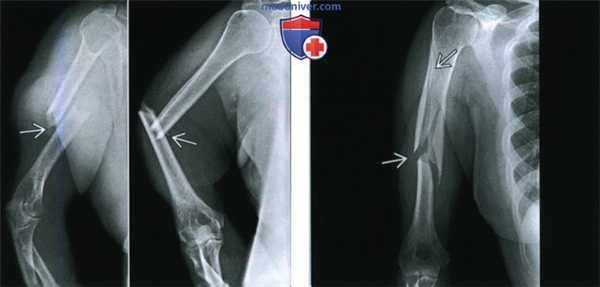

Диафизарные переломы

Переломы плеча в среднем отделе (диафизарные переломы плеча) возникают в результате падения на руку или удара по плечу, могут быть косыми, поперечными, винтообразными и оскольчатыми. Диафизарные переломы плеча нередко сочетаются с повреждением лучевого нерва. Возможно повреждение плечевых артерий и вен.

Клиническими признаками перелома плеча являются боли, отечность, деформация, крепитация костных фрагментов и патологическая подвижность плечевой кости. При переломах плеча с повреждением лучевого нерва пациент не может самостоятельно разогнуть пальцы и кисть. Для уточнения диагноза и выбора тактики лечения выполняют рентгенографическое исследование.

Переломы плеча без смещения обезболивают и фиксируют гипсовой шиной. При переломах плеча со смещением накладывают скелетное или лейкопластырное вытяжение, которое после появления рентгенологических признаков костной мозоли заменяют гипсовой лонгетой. Общий срок иммобилизации при диафизарных переломах плеча составляет 3-3,5 месяца.

При хорошо сопоставленных переломах плеча, сочетающихся с повреждением лучевого нерва, проводится консервативная терапия (адекватная иммобилизация перелома плеча, лекарственная стимуляция восстановления нерва, ЛФК, физиолечение). Если в течение 2-3 месяцев нет признаков регенерации нерва, выполняют операцию. Хирургическое лечение показано при многооскольчатых переломах плеча, невозможности закрытой репозиции, интерпозиции мягких тканей и повреждении сосудов. Фиксацию отломков осуществляют при помощи пластин, металлических штифтов или аппарата Илизарова.